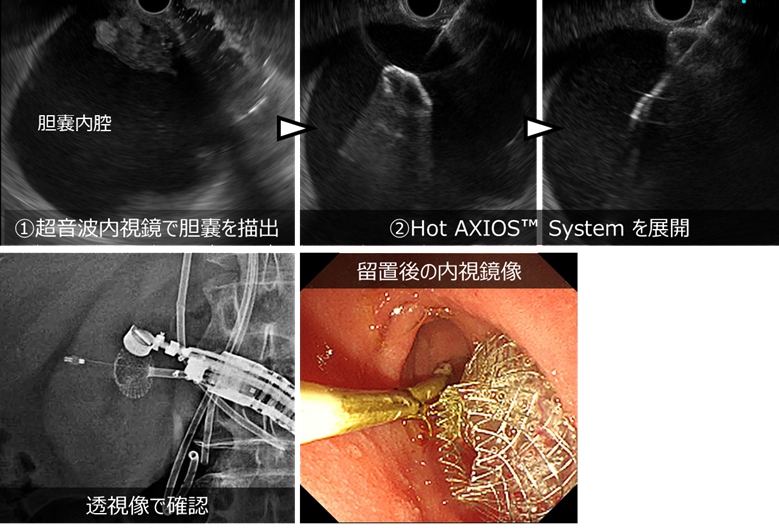

このデバイスは膵仮性嚢胞のドレナージだけでなく、胆嚢炎に対する超音波内視鏡下胆嚢ドレナージ(EUS-GBD)などにも応用され、使用可能となっています。

肝門部領域胆管癌に対して化学療法を施行中に胆嚢炎を発症した症例です。

EUSを用いて胆嚢を確認し、EUS-GBDを行いました。本症例では、ダンベル型金属ステントを用いたデバイスである Hot AXIOS™ System を使用して、胆嚢と消化管の間に通り道を作り、胆嚢内の膿や胆汁を排出しました。

胆嚢ドレナージを施行したところ、炎症は速やかに改善しました。その後、全身状態も回復し、化学療法を早期に再開することができました。